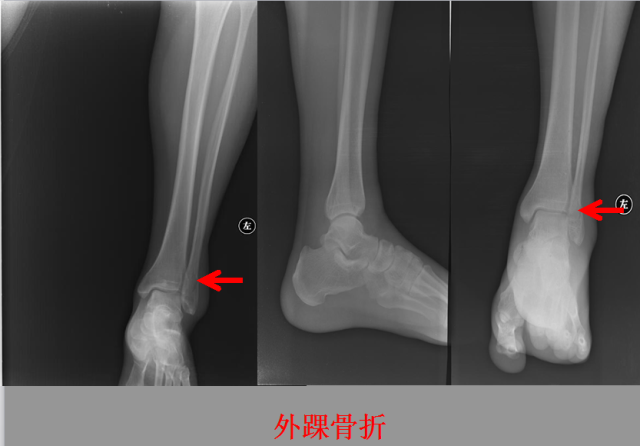

骨折篇

01

定义:骨折{Fracture}是指骨的完整性和连续性的折裂或粉碎。包括创伤性骨折、疲劳性骨折和病例理性骨折。 临床上以创伤性骨折*常见。